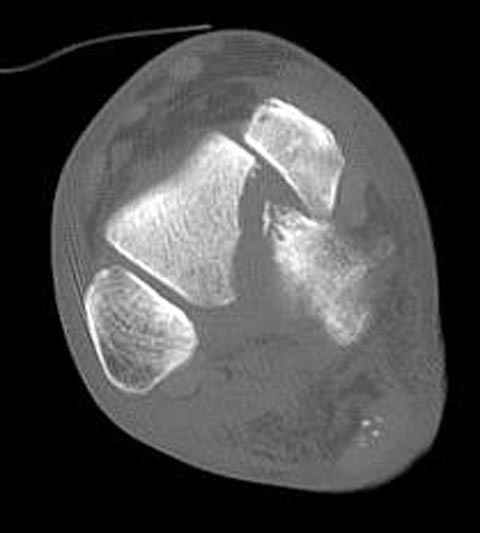

Уважаемые участники русского Ортофорума, поздравляю всех со всеми прошедшими праздниками: Новым годом, Рождеством, Hanukkah, Kwanzaa, желаю участникам всего наилучшего и здоровья.Повреждение таранной кости.Больной 81г автоавария, повреждение таранной кости, здесь снимки.

Вдогонку по поводу перелома таранной кости, больная 81, не страдает диабетом, перелом закрытый, в первый же день поступления ограничились временным наружным фиксатором (как на снимке).

Примеры на снимке...